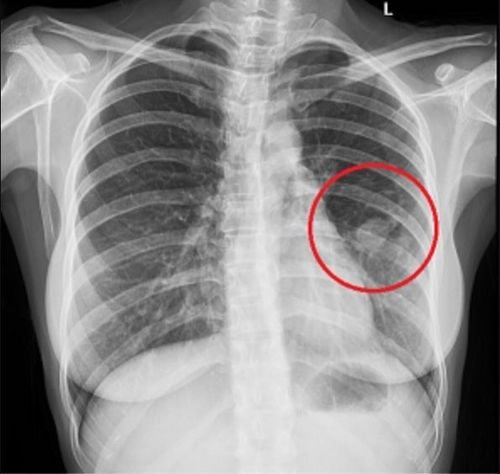

Tùy vào bản chất của từng cơ quan mà độ hấp thụ tia X của những cơ quan đó sẽ nhiều hay ít, cho ra hình ảnh trên phim chụp X – quang sẽ có màu đen, trắng, xám với những mức độ đậm nhạt khác nhau. Trên thực tế lâm sàng, một số trường hợp cho thấy được hình ảnh X – quang phổi màu trắng ở 1 hoặc cả 2 lá phổi của bệnh nhân, hay có khi là những hình ảnh X – quang phổi mờ hơn bình thường, nốt mờ ở đỉnh phổi hoặc phổi có đốm trắng và kem theo đó là những triệu chứng lâm sàng như ho ra đờm, khó thở thì đây sẽ là những dấu hiệu điển hình để định hướng chẩn đoán đến bệnh lý phổi màu trắng trong những trường hợp này. Đây là bệnh lý liên quan đến những rối loạn về hệ hô hấp do tình trạng không đủ oxy cung cấp cho phổi khiến hình ảnh phổi trên phim chụp X – quang là màu trắng một phần hay toàn bộ.

Bên cạnh những dấu hiệu lâm sàng như ho có đờm, ho khan, khó thở… thì một phương tiện cận lâm sàng giúp hỗ trợ chẩn đoán sẽ được chỉ định như chụp X – quang phổi hoặc các phương pháp chẩn đoán hình ảnh khác như chụp cắt lớp vi tính phổi. Những kết quả như hình ảnh X – quang phổi màu trắng hay chụp cắt lớp vi tính phổi thấy những đám màu trắng sẽ giúp định hướng tìm ra nguyên nhân gây bệnh, từ đó sẽ có những phương pháp chữa trị thích hợp. Để điều trị bệnh phổi màu trắng thì bên cạnh việc dùng thuốc theo phác đồ mà bác sĩ điều trị đưa ra thì bệnh nhân cũng cần thay đổi một số thói quen xấu trong phong cách sống của mình như từ bỏ việc hút thuốc lá để giảm thiểu nguy cơ mắc bệnh cho bản thân và cho người xung quanh, cũng như ngăn chặn khả năng xảy ra những biến chứng không mong muốn.

Phổi màu trắng là bệnh lý được chẩn đoán khi bệnh nhân có những biểu hiện bất thường về đường hô hấp như ho, khó thở… cùng với hình ảnh X – quang phổi màu trắng hoặc chụp cắt lớp phổi màu trắng. Đây là một bệnh lý nguy hiểm và có nguy cơ để lại những biến chứng nghiêm trọng với sức khỏe người bệnh, vì vậy cần được phát hiện và chữa trị sớm nhất ngay khi có thể.